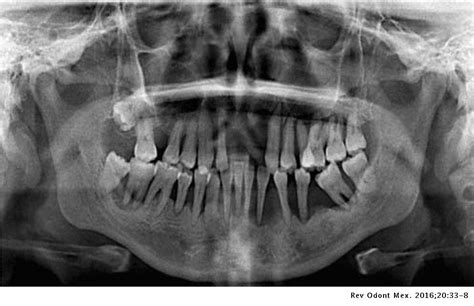

Paciente de sexo masculino, de 68 años de edad, no fumador. Sin trastornos sistémicos de importancia, asiste a mi consulta presentando el estado bucal que nos muestra la radiografía panorámica que el paciente nos trae por iniciativa propia.

Radiografía panorámica inicial

Luego de realizar la historia clínica, la ficha implantológica y el pedido de análisis de laboratorio rutinarios. Al cabo de dos meses se le solicita una nueva radiografía panorámica.

Radiografía panorámica prequirúrgica